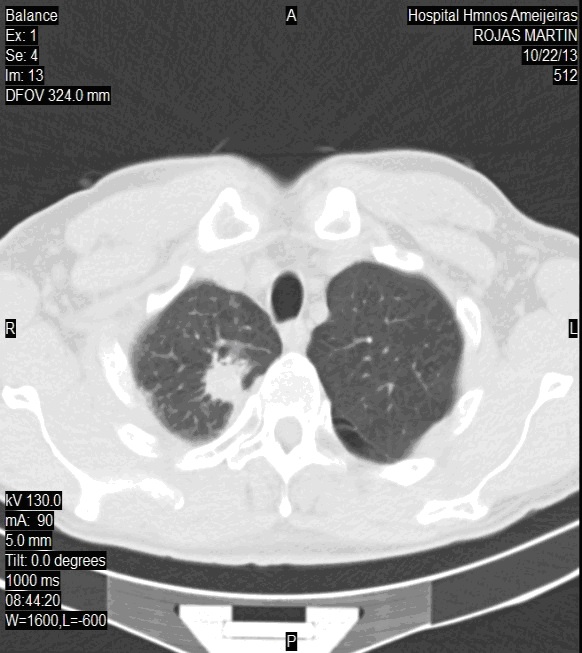

TAC simple de cráneo y tórax 30 de octubre de 2014

Cráneo: no hay signo de metástasis.

Tórax: en la parte interna de vértice derecho nódulo infiltrante que mide 2 cm, signos de fibrosis por RTP. Dilataciones bronquiales regionales. No otras lesiones pleuro-pulmonares ni óseas (imagen 2B).

IMAGEN 2B. TAC de tórax: 30 de octubre de 2014